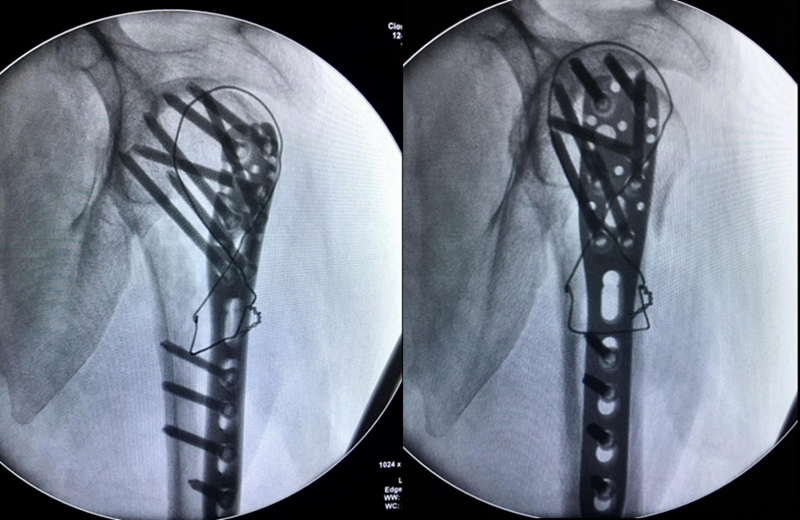

肩前外侧劈三角肌入路,三角肌前束和中间束肌肉间隙进入,双套固定技术加强固定。

图17 术中

术中C-臂检测:

图18 肱骨距螺钉固定确切